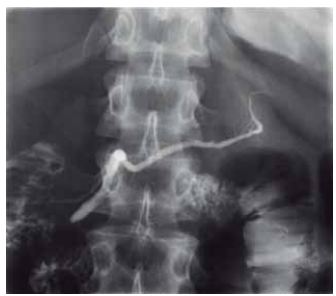

O exame radiológico contrastado com iodo, colangiopancreatografia retrógrada endoscópica, permite a visualização dos ductos biliares e pancreáticos. O ducto que

encaminha uma secreção rica em bicarbonato de sódio,

tripsina, quimotripsina, lipase, amilase e proteases, ao sistema digestório, é demonstrado pela radiografia a seguir:

(Arquivo pessoal; imagem usada com autorização)

A imagem refere-se ao ducto